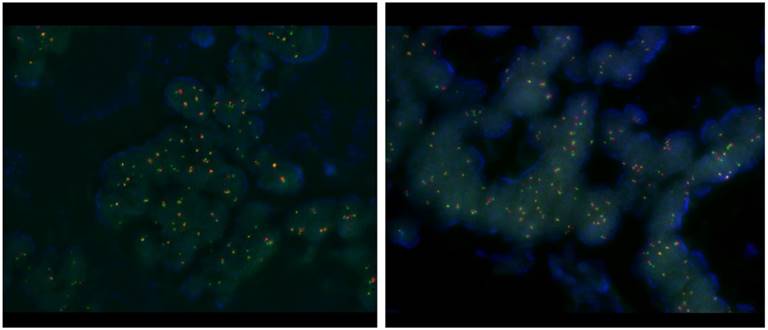

Patient. A 63-year-old man initially presented with stage III, rectosigmoid colon cancer in 2013. He underwent lower anterior resection for the primary lesion and then received eight cycles of adjuvant XELOX (capecitabine and oxaliplatin) chemotherapy. During regular surveillance, at 2015, the patient suffered from an abrupt headache. Brain imaging for the patient revealed a single brain mass. Patient received a curative intent brain surgery for the single brain mass suggesting a malignant primary brain tumor (Fig. 1). After pathologic confirmation for tumor, we generated PDCs from the patient. Finally, this resected brain lesion was confirmed in a metastatic recurrent colon cancer. NCOA4-RET fusion was detected by FusionPlex using the resected tumor sample and then reconfirmed by fluorescence in situ hybridization (FISH) test (Fig. 2). We also confirmed the RET fusions by a qPCR in matched PDCs (Fig. 3).

Figure 2

Fluorescence in situ hybridization (FISH) test.

RET translocation with fluorescence in situ hybridization (FISH). FISH was performed using the ZytoLightR SPEC RET Dual Color Break Apart Probe Kit (ZytoVision, Bremerhaven, GERMANY) for RET. This probe is designed to detect translocation involving the chromosomal region 10q11.21 harboring the RET (rearranged during transfection proto-oncogene) gene. It is a mixture of two direct labeled probes hybridizing to the 10q11.21 band. The orange fluorochrome direct labeled probe hybridizes proximal to the RET gene, the green fluorochrome direct labeled probe hybridizes distal to that gene.